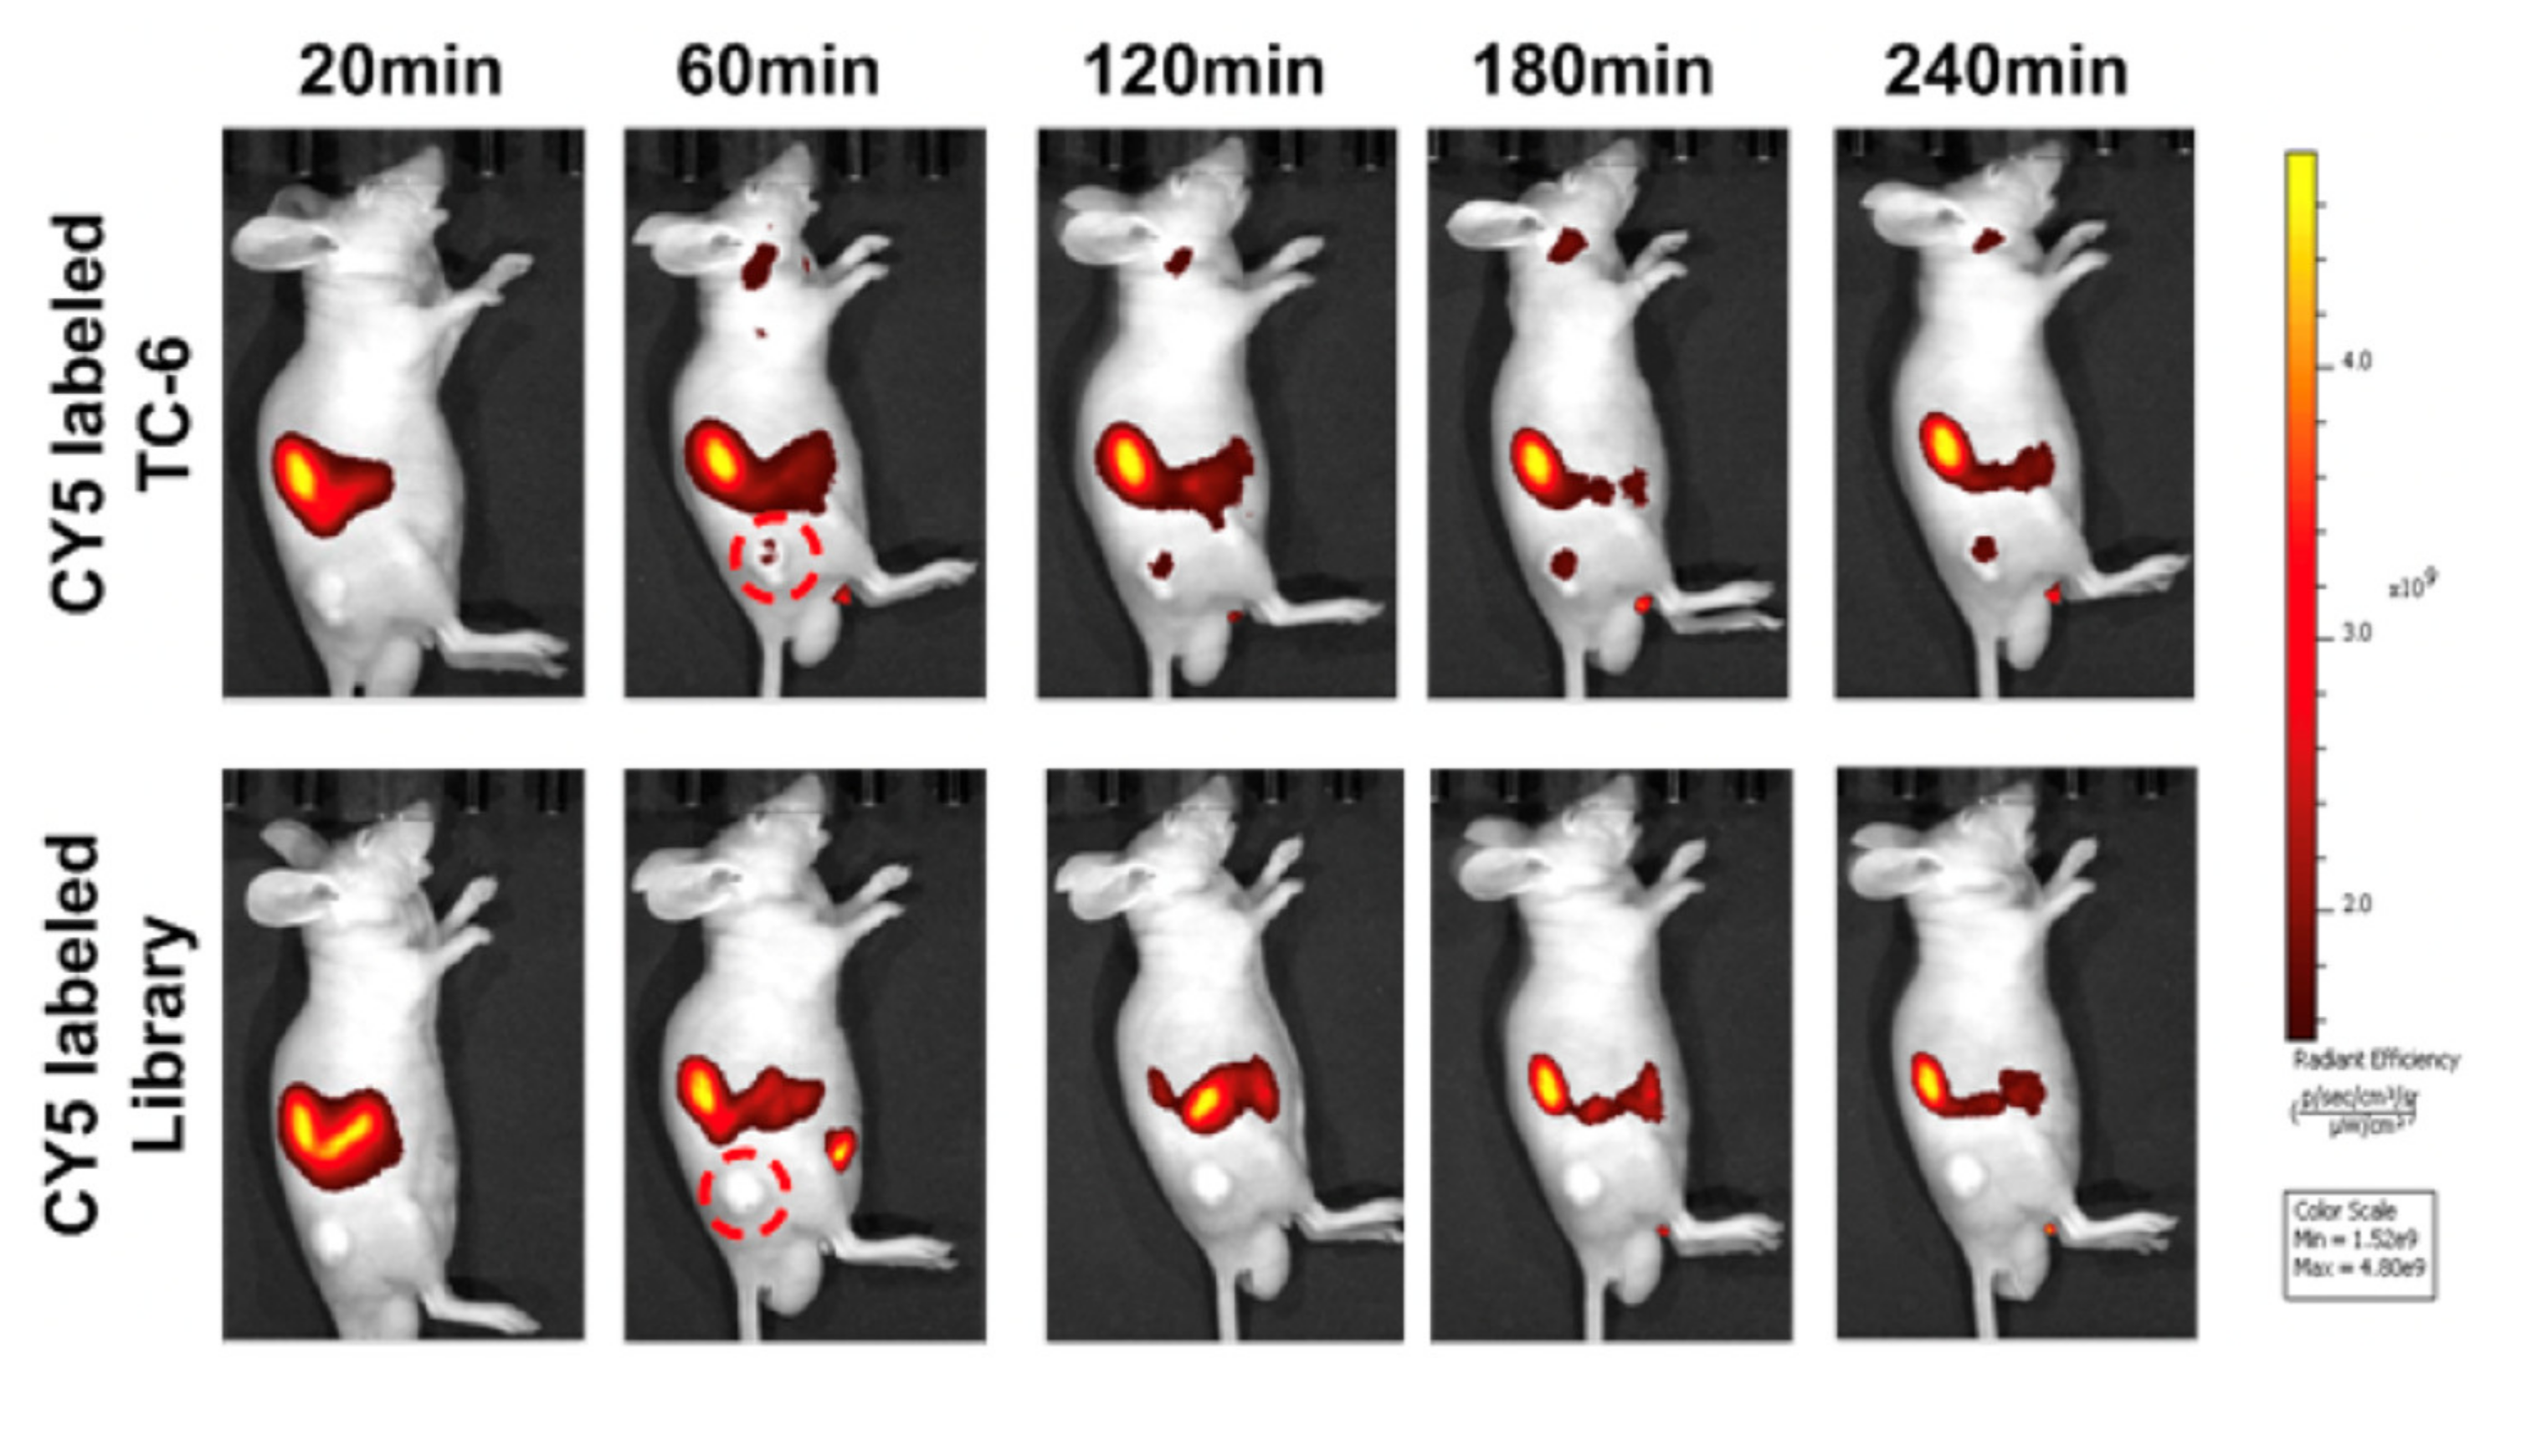

5.1.2. PTC Tissue-Targeting Probes

- Zhong, W.; Pu, Y.; Tan, W.; Liu, J.; Liao, J.; Liu, B.; Chen, K.; Yu, B.; Hu, Y.; Deng, Y.; et al. Identification and Application of an Aptamer Targeting Papillary Thyroid Carcinoma Using Tissue-SELEX. Anal. Chem. 2019, 91, 8289–8297. [Google Scholar] [CrossRef]